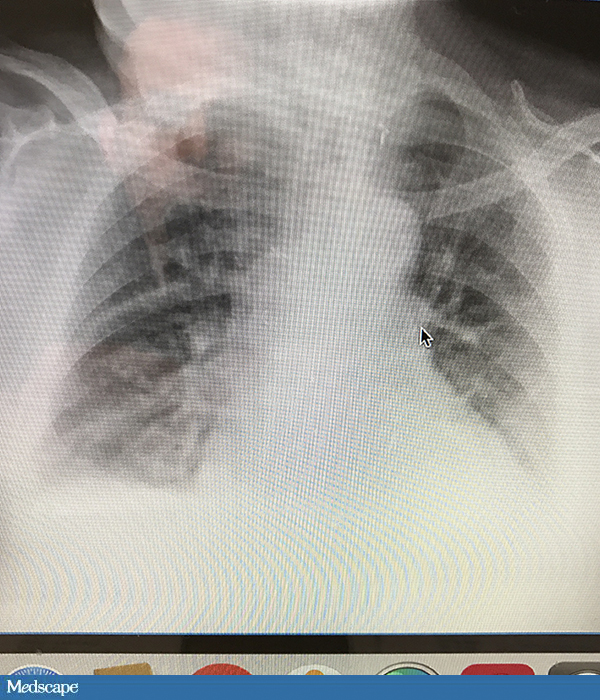

2019-03-15 20:18 757 氧氟沙星 头孢唑林 克拉维酸 多西环素 呋塞米 磷霉素 哌拉西林 阿莫西林 万古霉素 胰岛素 头孢氨苄 头孢曲松 强的松 舒巴坦 阿奇霉素 头孢他啶 糖尿病 酸中毒 头痛 淋巴水肿 呼吸急促 疼痛 尿

,来看看你是不是能做出正确的诊断吧。 病例1学生,呼吸道不适高校学生,21岁,7天前